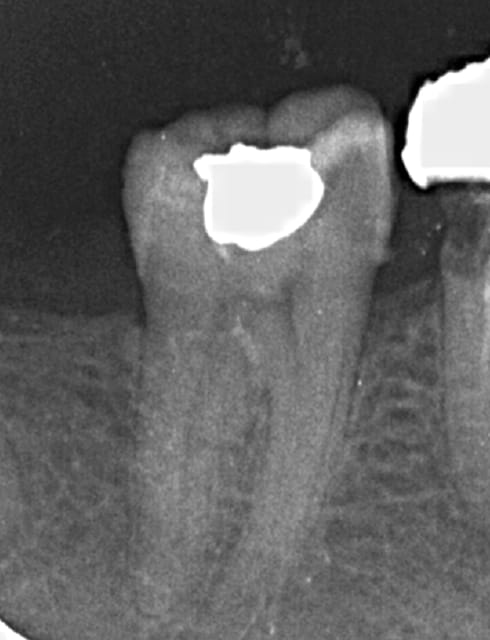

Juste pour prouver qu'on peut tout faire avec Mc Spadden, le derviche écossais:

Canal large, on est allé au F5 sans toucher les bords, cône calibré à 55 à l'apex, thermocompacteur à 3mm de la LT. Pas d'anesthésie.

Je l'utilise de mieux en mieux mais c'est vrai qu'il y a une petite douleur ressentie par les patients. Je descend super bas, mais je vérifie que j'ai un bon tug back à chaque fois (je descends à 2-4 mm de l'apex), avec un 40 ou un 30 la plupart du temps.